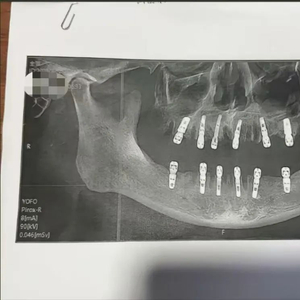

近日,浙江永康市的舒女士反映,其父亲黄某在当地德维口腔医院一次性拔除23颗牙齿,并在同日种植12颗牙齿。随后疼痛不止,13天后因心脏骤停死亡。消息随即引发热议。

舒女士介绍,父亲黄某8月14日在德维口腔医院接受牙科手术。据黄某签署的种植手术同意书显示,本次治疗拔牙23颗、种植牙齿12颗,并且均为即刻修复,即“当天拔、当天种”,负责治疗的医师为袁某。

舒女士说,术后黄某的牙齿疼痛不止,于8月28日因心脏骤停死亡。